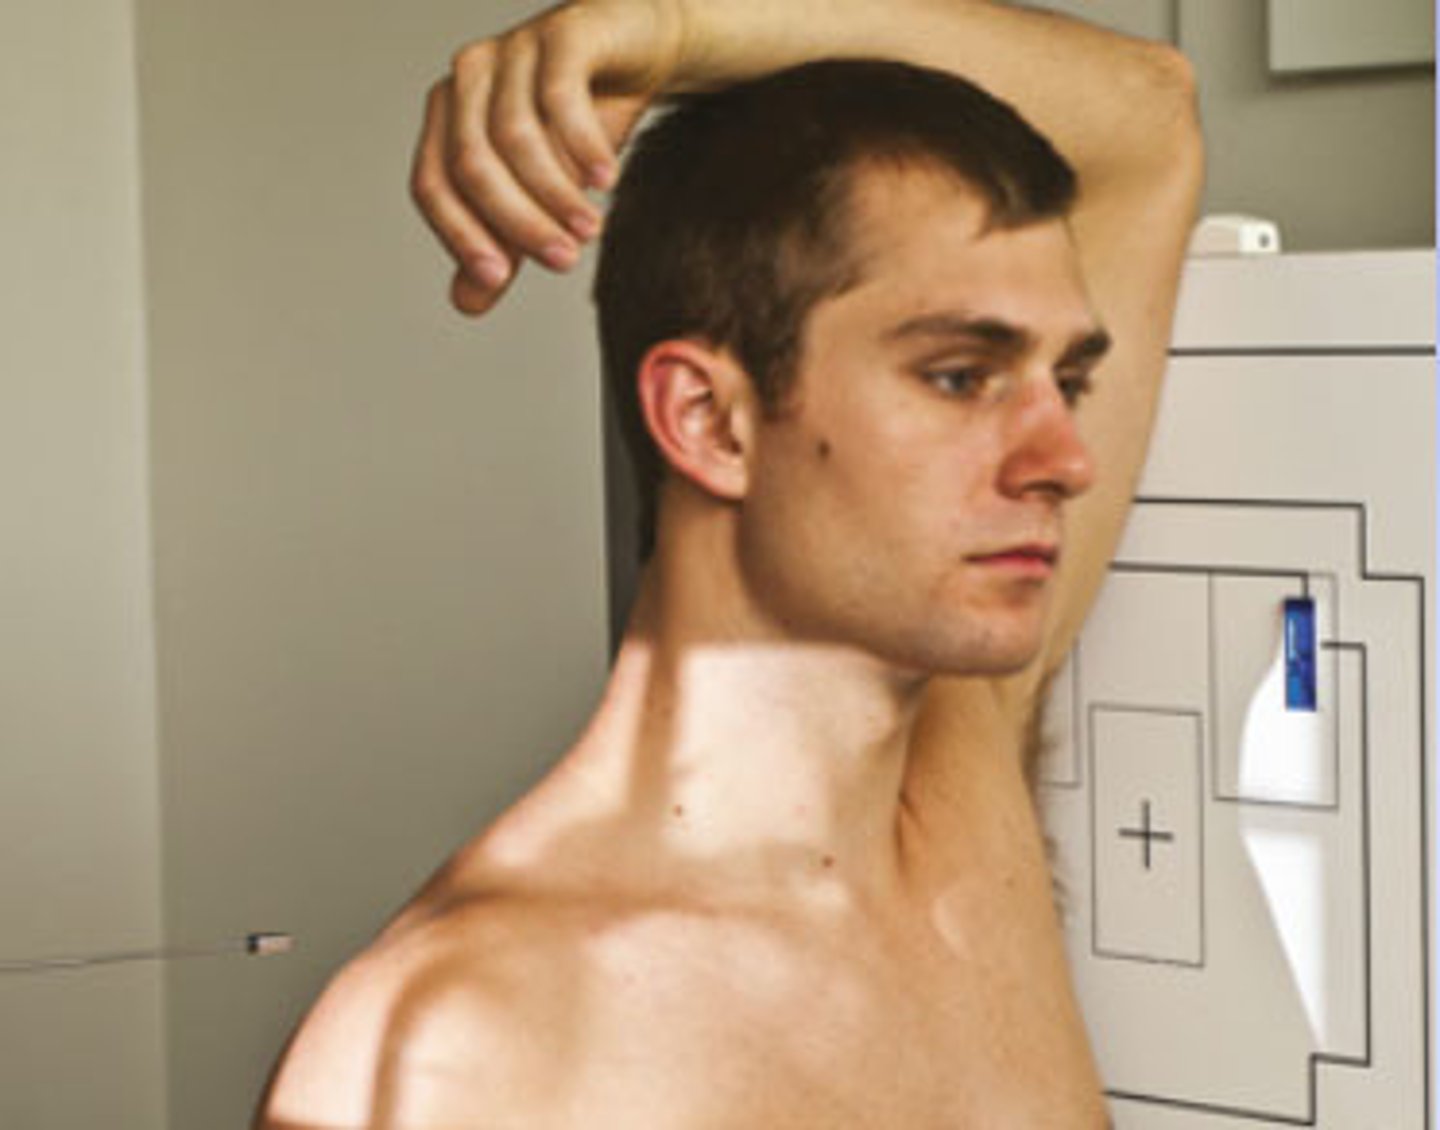

Go through the STAMPSBC list for the Swimmers C-spine

S - shielding around waist

T - 120 mAs @ 80 kVp

A - no angle

M - marker along curve of neck

P - left side against board, left arm above head

S - 72

B - suspend breathing after expiration

C - 14 x 17 lengthwise, can collimate side to side

Where do you center for the Swimmers C-spine?

1 inch above jugular notch

If the PT cannot separate humeral heads enough on the Swimmers C-spine what do you use?

3 - 5 degree caudad angle

Why is a Swimmers C-spine view done?

because C7 wasn't seen on normal Lateral